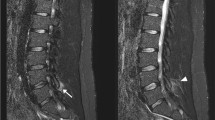

Magnetic resonance imaging (MRI) remains the most reliable method to diagnose spondylodiscitis, due to its high sensitivity (96%), high specificity (94%), and capability to provide detailed data on paraspinal tissues and the epidural space [51, 53, 57]. Typical findings in patients with spondylodiscitis are hypointense discs and vertebral bodies in T1-weighted images and hyperintense signals of the same structures in T2-weighted images.

Male patient, 61 years old, suffering from a septic arthritis of the left ankle joint, chronic alcoholism abuse, presenting with a weakness for abduction (3/5) of the left upper extremity for 2 weeks. Laboratory results show elevated inflammatory parameters (CRP: 5.0 mg/dl, leukocytes: 13.0) Blood cultures reveal Staphylococcus aureus, and Amoxicillin 2.2 g 3× is started. Imaging depicts a spondylodiscitis C4/5 and C5/6 accompanied by intraspinal and prevertebral abscess, plus kyphotic deformity of the cervical spine. (see image a and b) A (1) corporectomy with anterior plating C3–6 and vertebral body replacement (image c) plus (2) dorsal stabilization C3–7 was performed. (image d) Intraoperative biopsy confirms Staph. aureus, Imipenem + Fosfomycin therapy is continued and inflammatory parameters decrease

Female patient, 73y, suffering from acute myeloid leukemia (AML), presenting with refractory low back pain following a periradicular infiltration 1 month previously. CRP is elevated (15.8 mg/dl), leukocytes are low due to AML (4.1) and blood culture results are negative. Imaging is highly suspicious for spondylodiscitis L5/S1 with a prevertebral abscess (image a and b). Percutaneous instrumentation (L5/S1) is performed (image c) and empiric antibiotic therapy is started (Dalacin + Ciproxin). CRP decreases over time (3.8 mg/dl 2 weeks after instrumentation) and a complete remission of the symptoms after 2 months (image d) is achieved